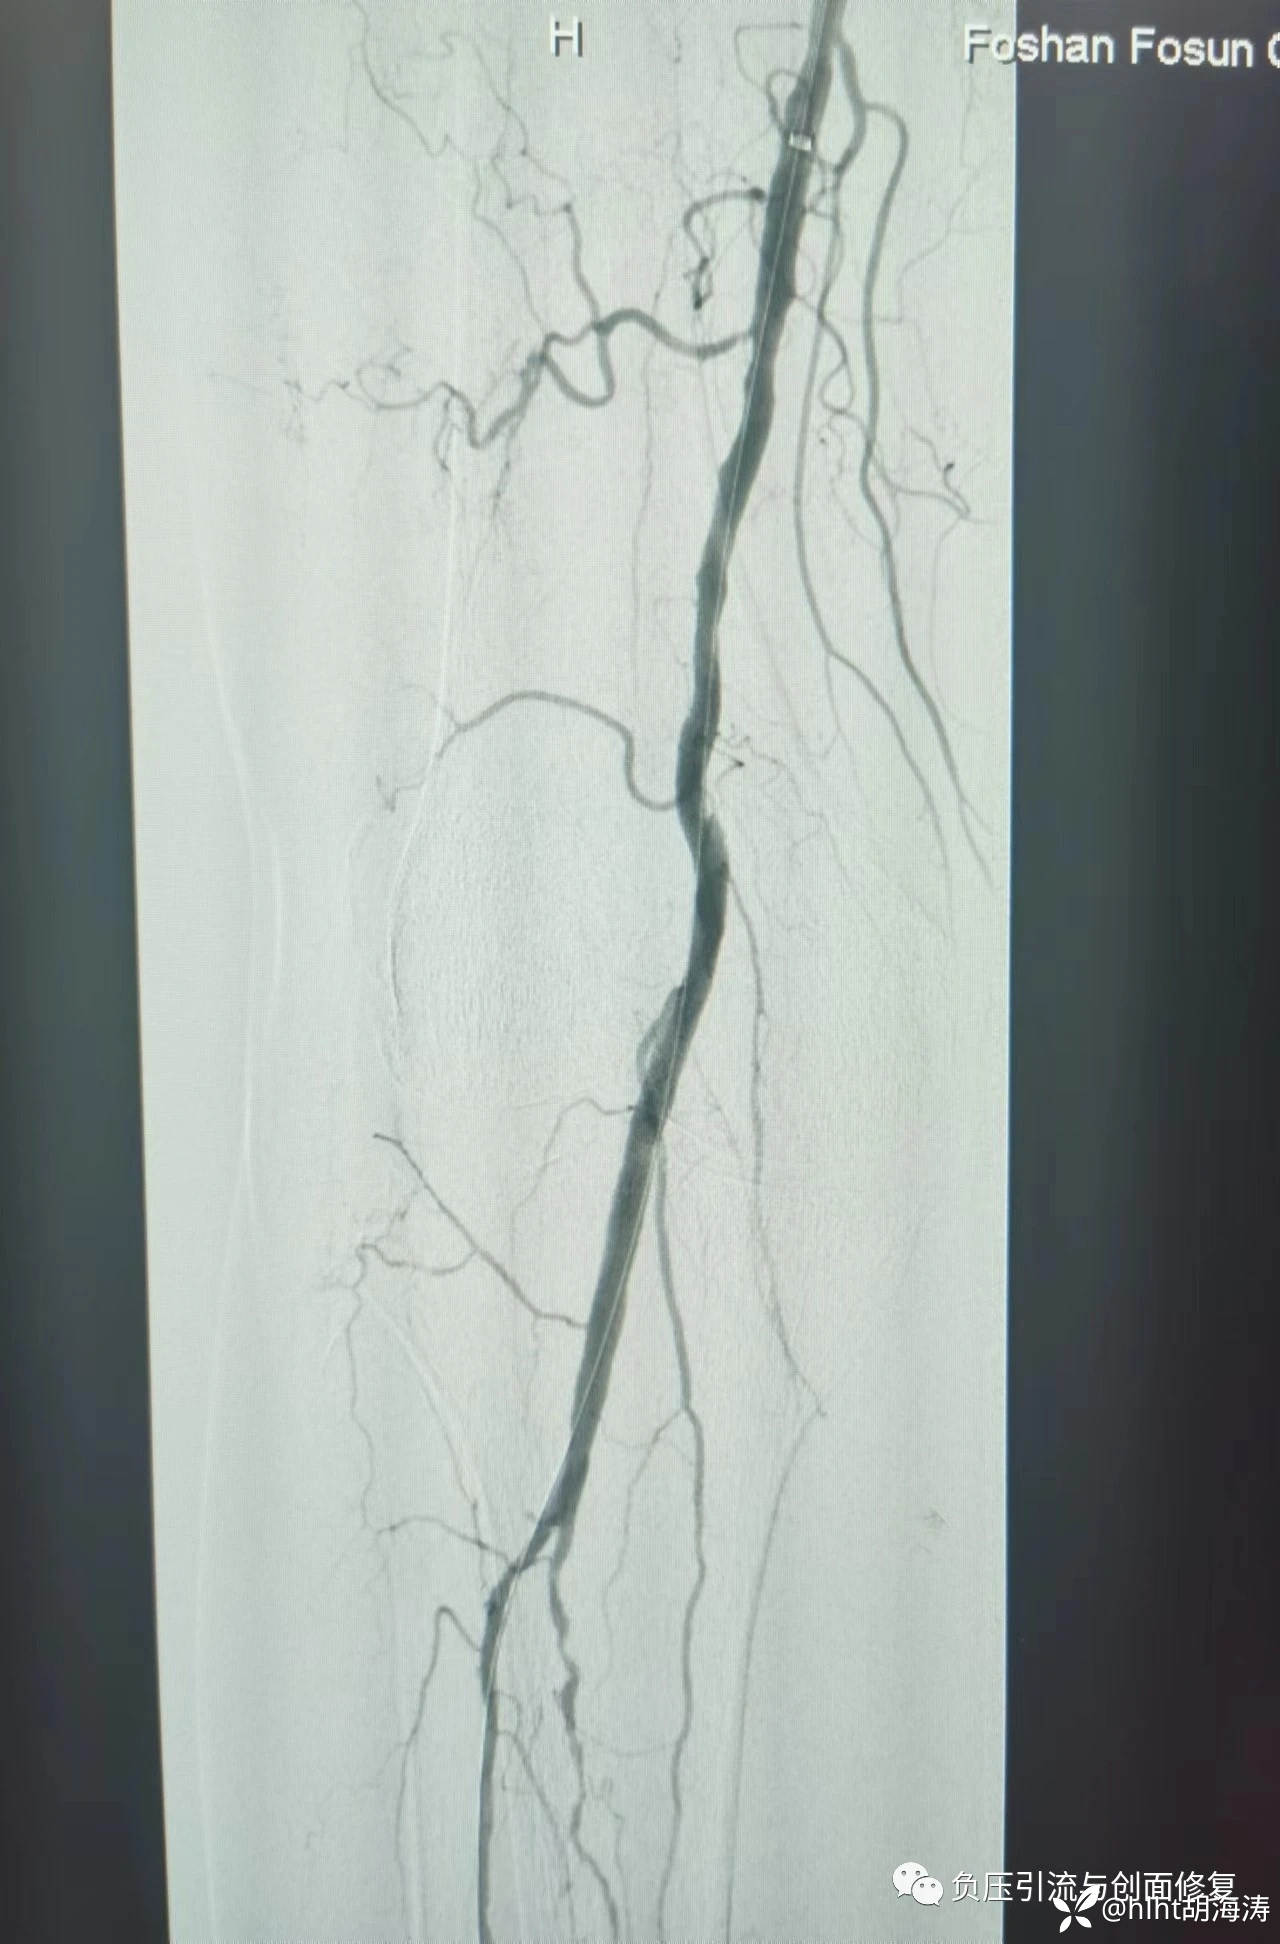

造影:发现股动脉远端重度狭窄,腓动脉和胫后动脉完全闭塞,胫前动脉轻中度狭窄部分重度狭窄;

患者运气也很好:导丝顺利经过各闭塞和狭窄部位,到达足背动脉;

球囊扩张从2mm开始,胫前动脉到4mm,股动脉远端到6mm,再次造影,血流通畅,没有夹层,就没放支架,单纯球囊扩张,手术时间90分钟;